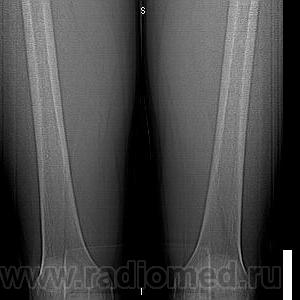

Молодой человек, спортсмен, профессионально занимается футболом с вытекающими последствиями, был обследован на МРТ ,область т/бедренного сустава, в диафизе обнаружилась якобы киста, направлен на КТ. Результаты КТ:

Публикации: 16

Молодой человек, профессионально занимается футболом, был обследован на МРТ по поводу травмы тазобедренного сустава. Со стороны сустава грубой патологии не выявлено, но в диафизе бедренной кости обнаружили якобы кисту. Был обследован на КТ. Ваше мнение?

Эностальная реакция или отколы мелких фрагменов костной ткани изнутри?

При биопсии оказалась хондросаркома. Боли в этой области не беспокоили. "Зазубрина" на контуре кости при реконструкции-артефакт в результате движения конечности.

По КТ картине было высказано предположение в дифференциальном ряду, но для нас, честно говоря, биопсия была полной неожиданностью.